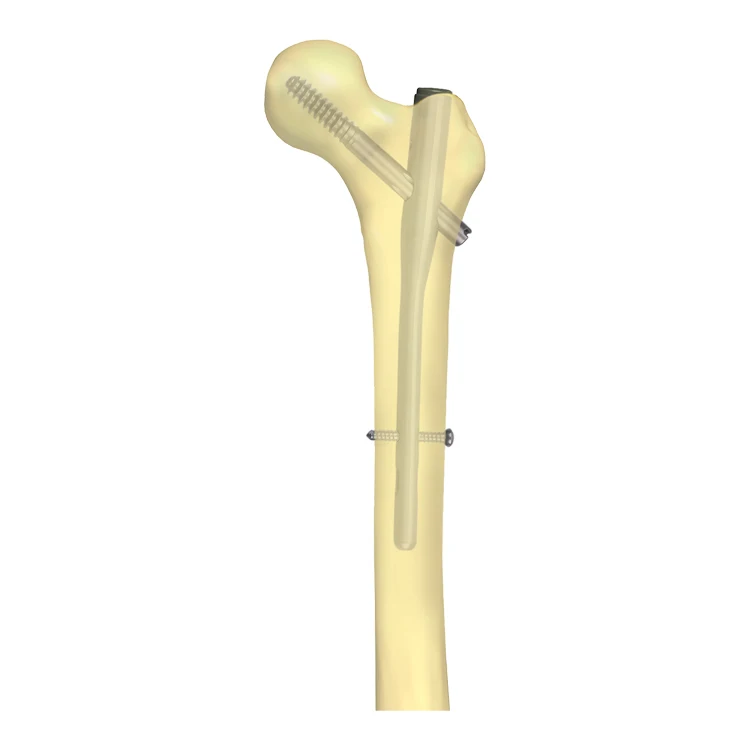

Интрамедуллярный стержень

Интрамедуллярный стержень 115 фотографий